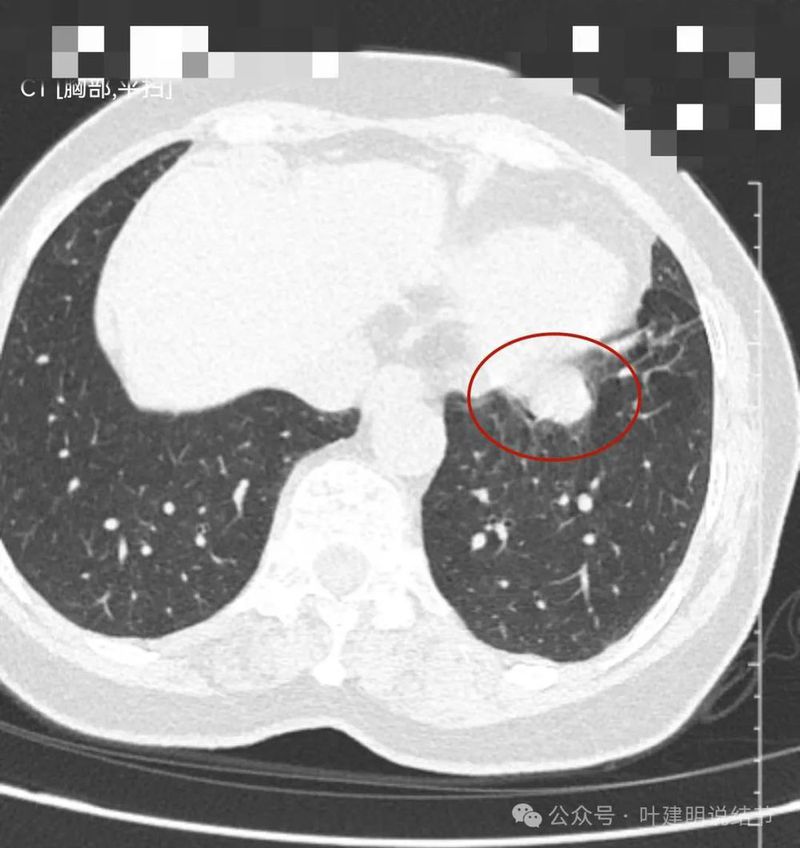

左下实性结节,明显有膨胀感,边缘虽然光滑,但给人感觉不舒服,恶性的可能性大些。

再看左下主病灶连续层面与重建影像:

冠状位见病灶与周围结构有间隙,说明不像炎性,如果是炎症,挨这么近,一般会搭牢的。